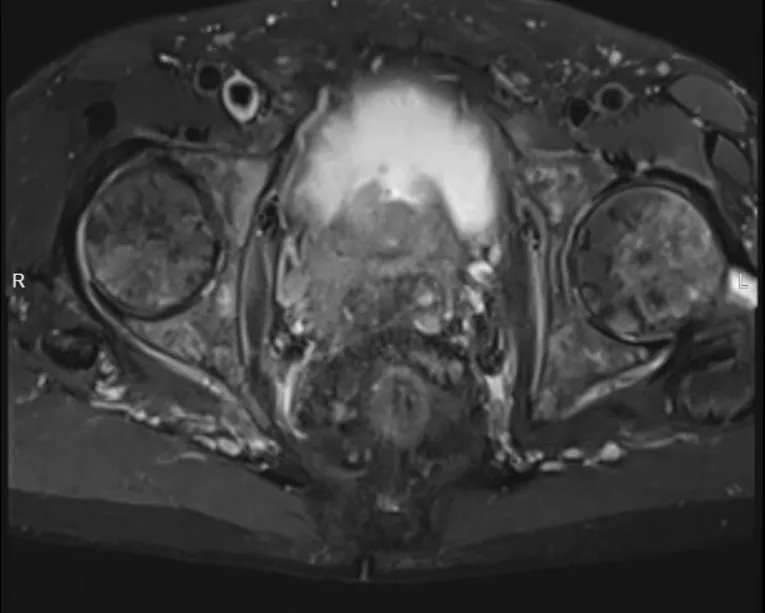

前列腺增强MRI (2025-5-14)

1. 考虑前列腺癌累及两侧精囊腺,膀胱颈及直肠前壁受累可能,请结合临床。

2. 盆腔及两侧髂血管旁多发肿大淋巴结,转移可能。

3. 骨盆、两侧股骨上段及所示腰骶椎信号不均匀伴强化,转移可能,建议骨ECT检查。

4. 盆底软组织局部水肿。